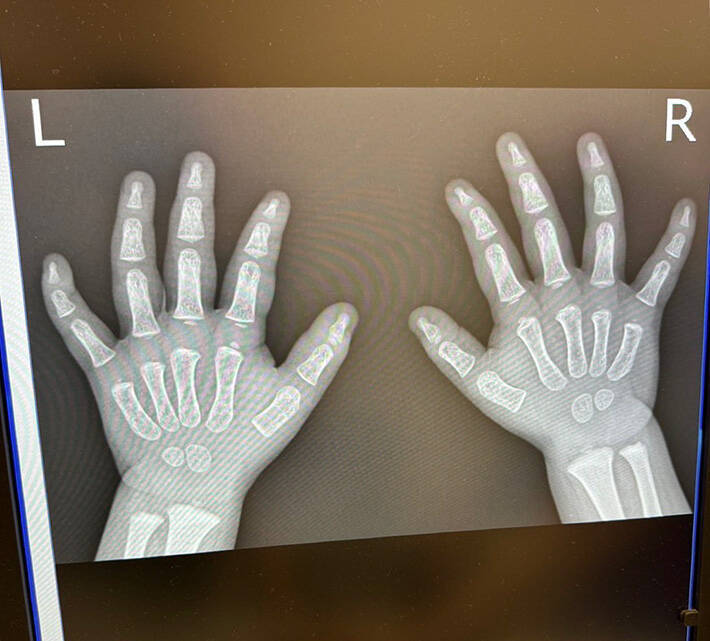

病院で息子の手のレントゲンを撮ったら?

ココ3(@shonancoco3)さんはある日、手を痛めた1歳の息子さんを病院に連れて行ったといいます。

骨折などの可能性を考え、医師は両手のレントゲンを撮影。場合によっては、重大なケガが判明する可能性もあるため、ココ3さんは気が気でなかったでしょう。

…しかし、その後写っていたモノを見た医師とココ3さんは、笑い合う事態に!

理由が分かる、実際のレントゲン写真をご覧ください。

か、かわいすぎる!

そこには発達途中の骨がはっきりと写っており、レントゲン写真ではあるものの、ムチッとした肉感が伝わってきます…。

我が子のかわいさを熟知しているココ3さんでも、骨格までかわいいとは驚いたことでしょう。なおさら、愛おしさがこみ上げますね!

幸い、息子さんは大事には至らなかったようです。

かわいすぎるレントゲン写真には、悶絶した人が続出した模様。13万件を超える『いいね』と、さまざまな感想が寄せられました!

・確かに笑える!かわいい生き物は骨までかわいいんだな。

・子供の骨ってつながっている様で、つながっていないのよね。ぽちゃぽちゃ感がたまらん…。

・世界一かわいいレントゲンだろ、これ。ギネスブックに載りなぁ!?

・尊い!「健やかに穏やかに育つのじゃぞ」という気分。

病院で我が子のかわいさを目の当たりにするとは、ココ3さんも予想していなかったでしょう。

『世界一かわいいレントゲン写真』は、ココ3さんと医師をはじめ、多くの人を笑顔にしたようです!